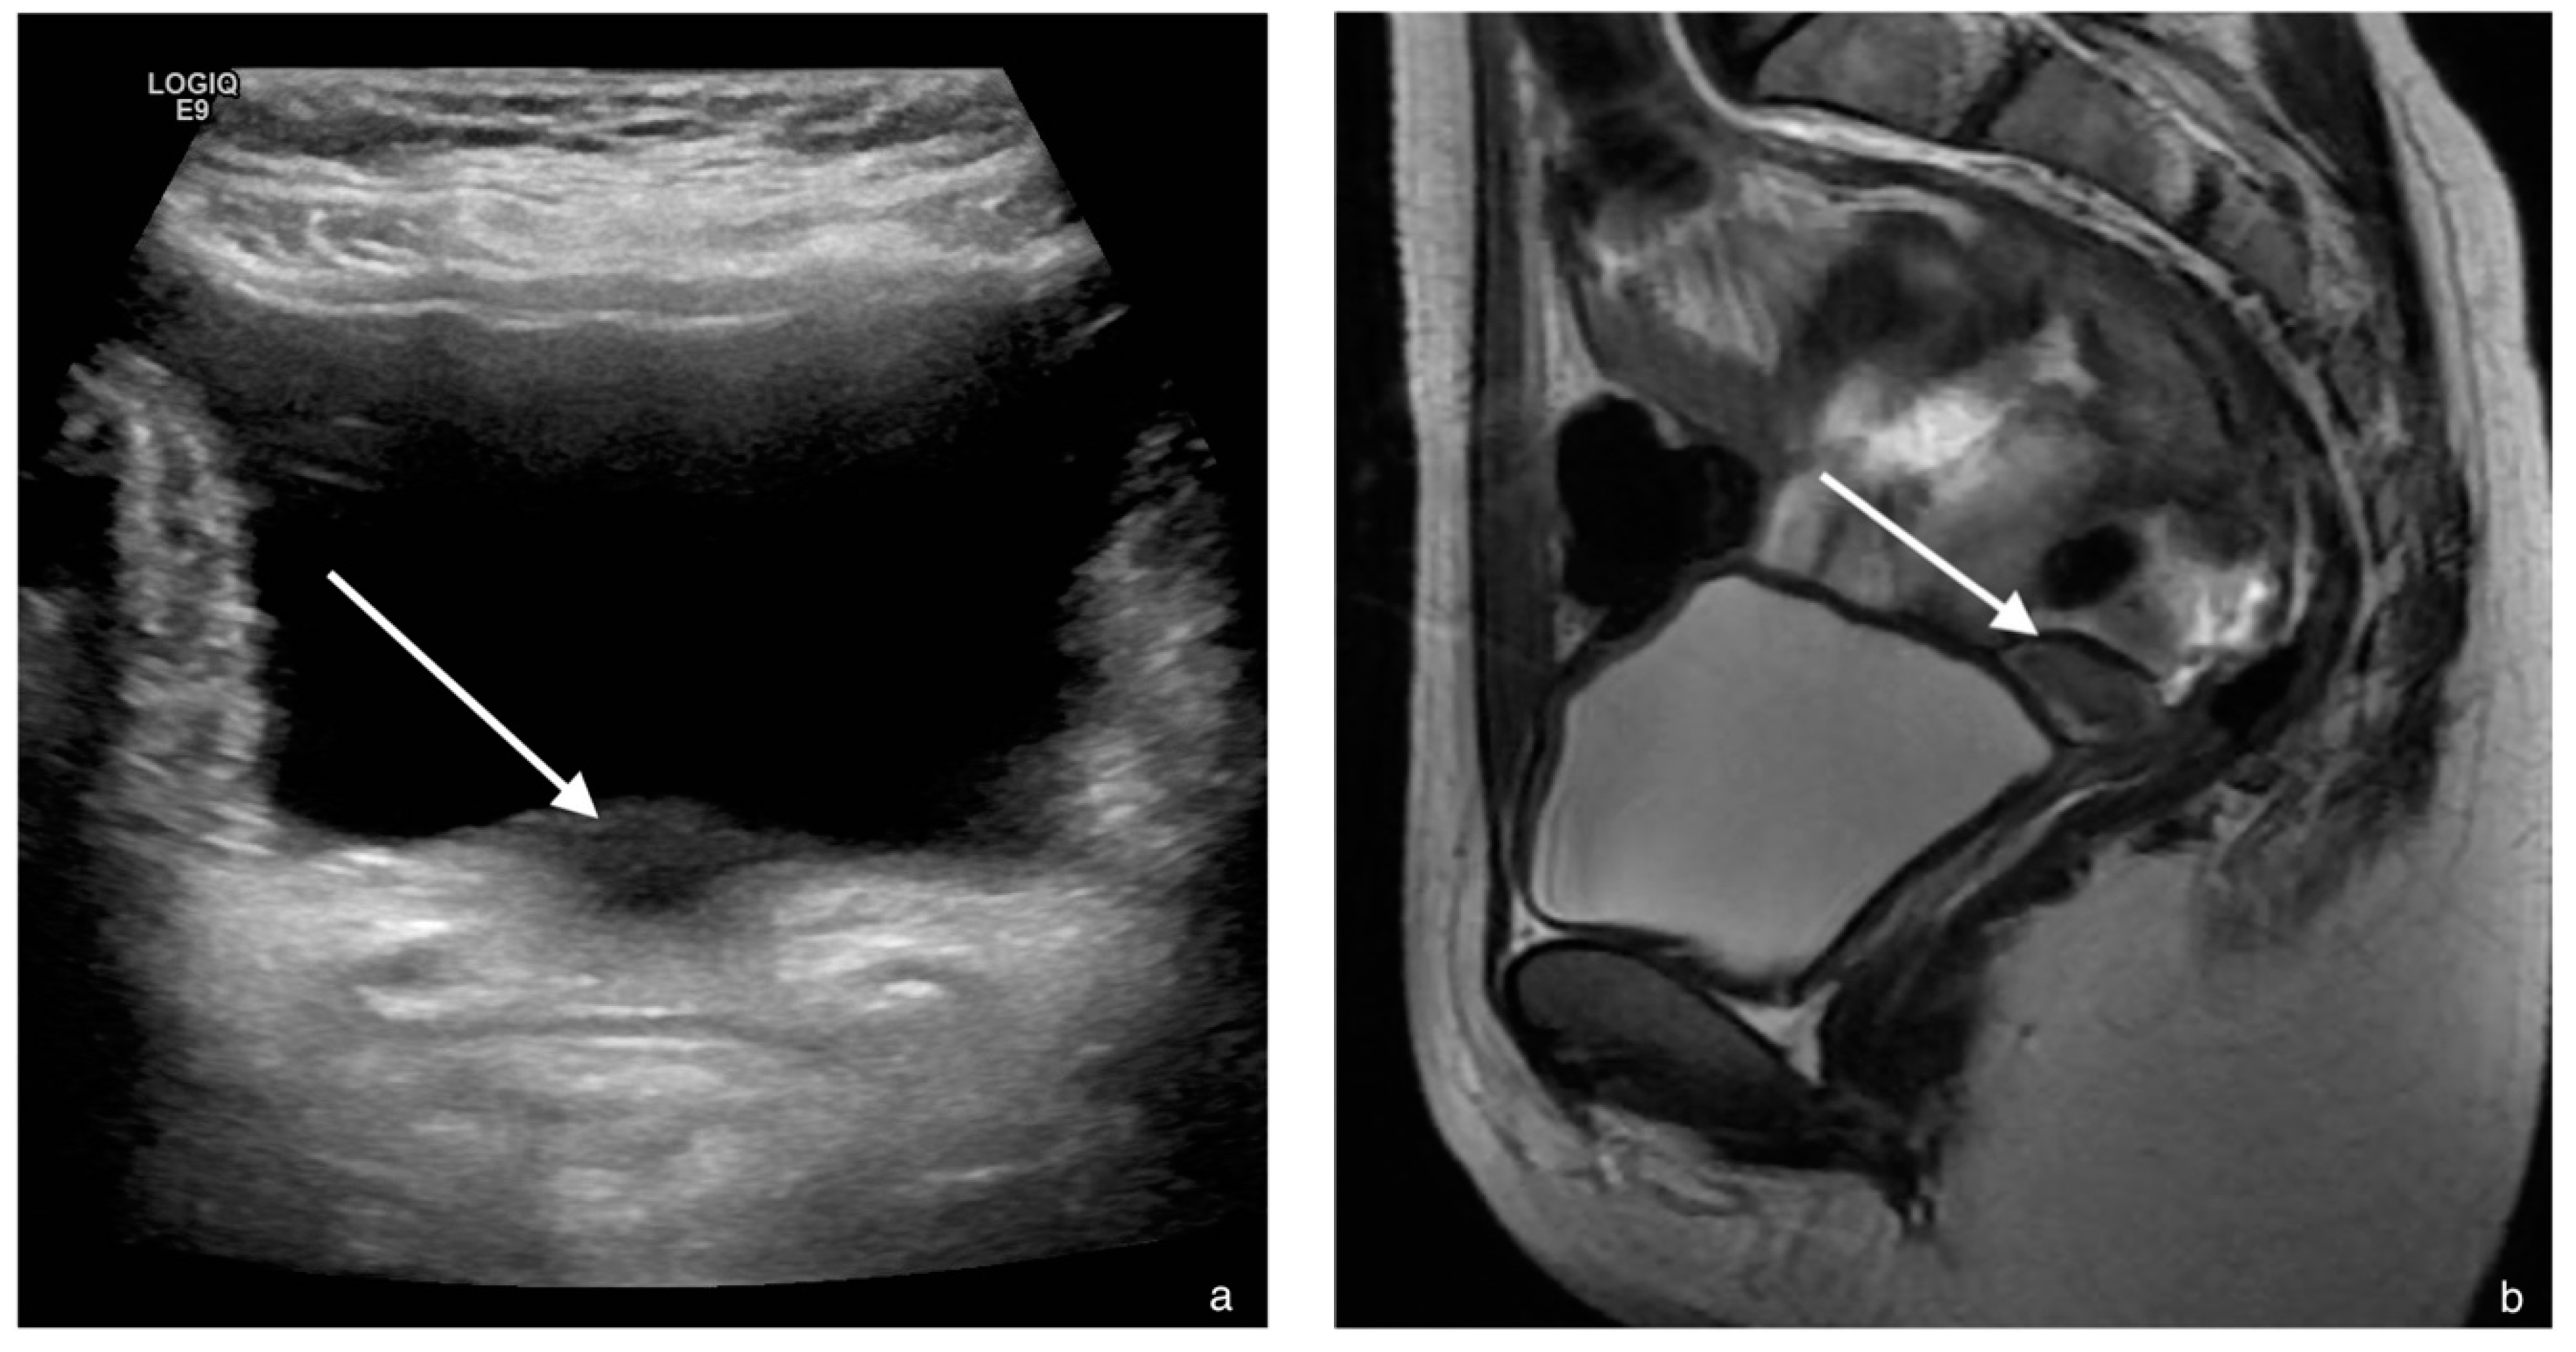

4. Case 3

| MRI report on primary investigation | Absent uterus, impression of hypoplastic vagina. Normal multicystic ovaries | Absent uterus and presence of a short vagina. Normal ovaries | Normal multicystic ovaries and a small uterus of 2.3 × 1.3 cm, described as rudimentary uterus | |

| MRI after referral | Lipofibromatous tissue at location of the uterus, no endo- myometrial or cervical structures. Normal multicystic ovaries | Underdeveloped Müllerian structures. Gonads with (ovo)testicular aspect | Small uterus with normal endo- and myometrial tissue, normal multicystic ovaries | |